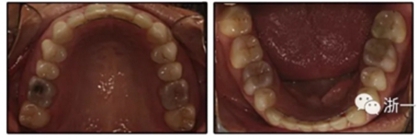

患者決定采用非手術(shù)治療方法,側(cè)貌沒有任何預(yù)期的變化。治療后面部照片(圖5)顯示她改善的微笑和側(cè)貌,包括尖牙保護合。由于先天性第一前磨牙缺失,右磨牙關(guān)系為III類。治療后牙齒石膏模型(圖6)顯示實體牙齒交錯排列情況,并且全景X線片顯示可接受的牙根平行度而且沒有牙根吸收表現(xiàn)(圖7)。最終的頭影測量片(圖7)證實了面部評估,并且描跡圖顯示深覆蓋的改善,同時保持上頜切牙位置并通過測量ANB角度和Wits評估改善骨性II級關(guān)系(表)。治療前后的疊加圖顯示由于下頜切牙前傾的增加改善了下唇平衡(圖8)。如相關(guān)治療計劃所預(yù)測的那樣,B點出現(xiàn)。A進行牙科錐形束計算機斷層掃描以記錄下頜前牙區(qū)的骨質(zhì)變化。如預(yù)期的那樣,由于治療導(dǎo)致該區(qū)域的骨量增加(圖9)。

最終評估結(jié)果如下:(1)美觀改善; (2)達到了生理功能; (3)患者對治療結(jié)果完全滿意; (4)上頜尖牙的角度和下頜切牙的傾斜度有所改善(表); (5)形成了穩(wěn)定的牙周終點,并觀察到附著齦的厚度改善; (6)病人會從下頜前移中受益,但她不想改變她的側(cè)貌; (7)長期變化(6年)是穩(wěn)定的,在B點再生的骨保持穩(wěn)定,咬合關(guān)系得到改善(圖10和11;表)。